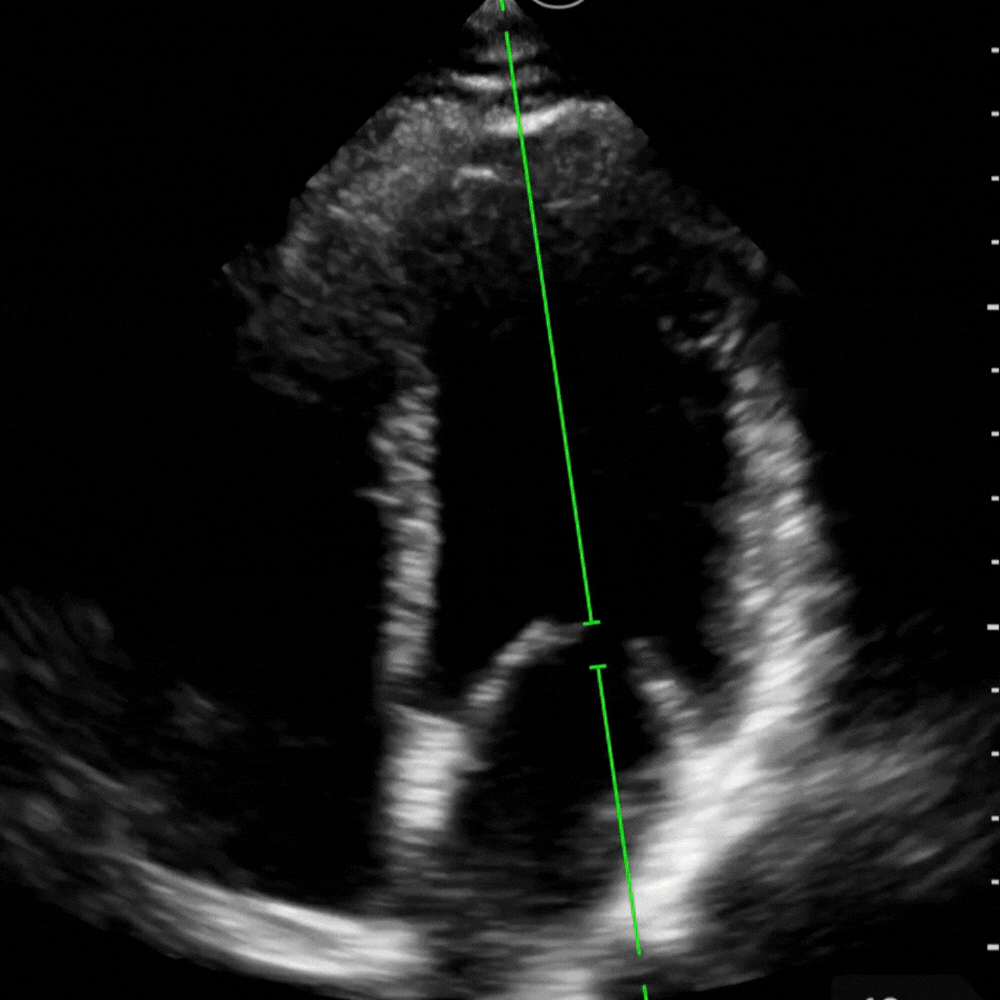

En A4C :

- Centrer la vue sur la valve mitrale

- Placer le curseur juste sous les feuillets mitraux (cf. photo ci-dessous)

- Activer le Doppler pulsé (PW)

- Obtenir les deux ondes du remplissage : onde E (remplissage précoce) et onde A (contraction atriale)

- Mesurer les pics de vitesse de E et A.

- Calcul automatique du rapport E/A.